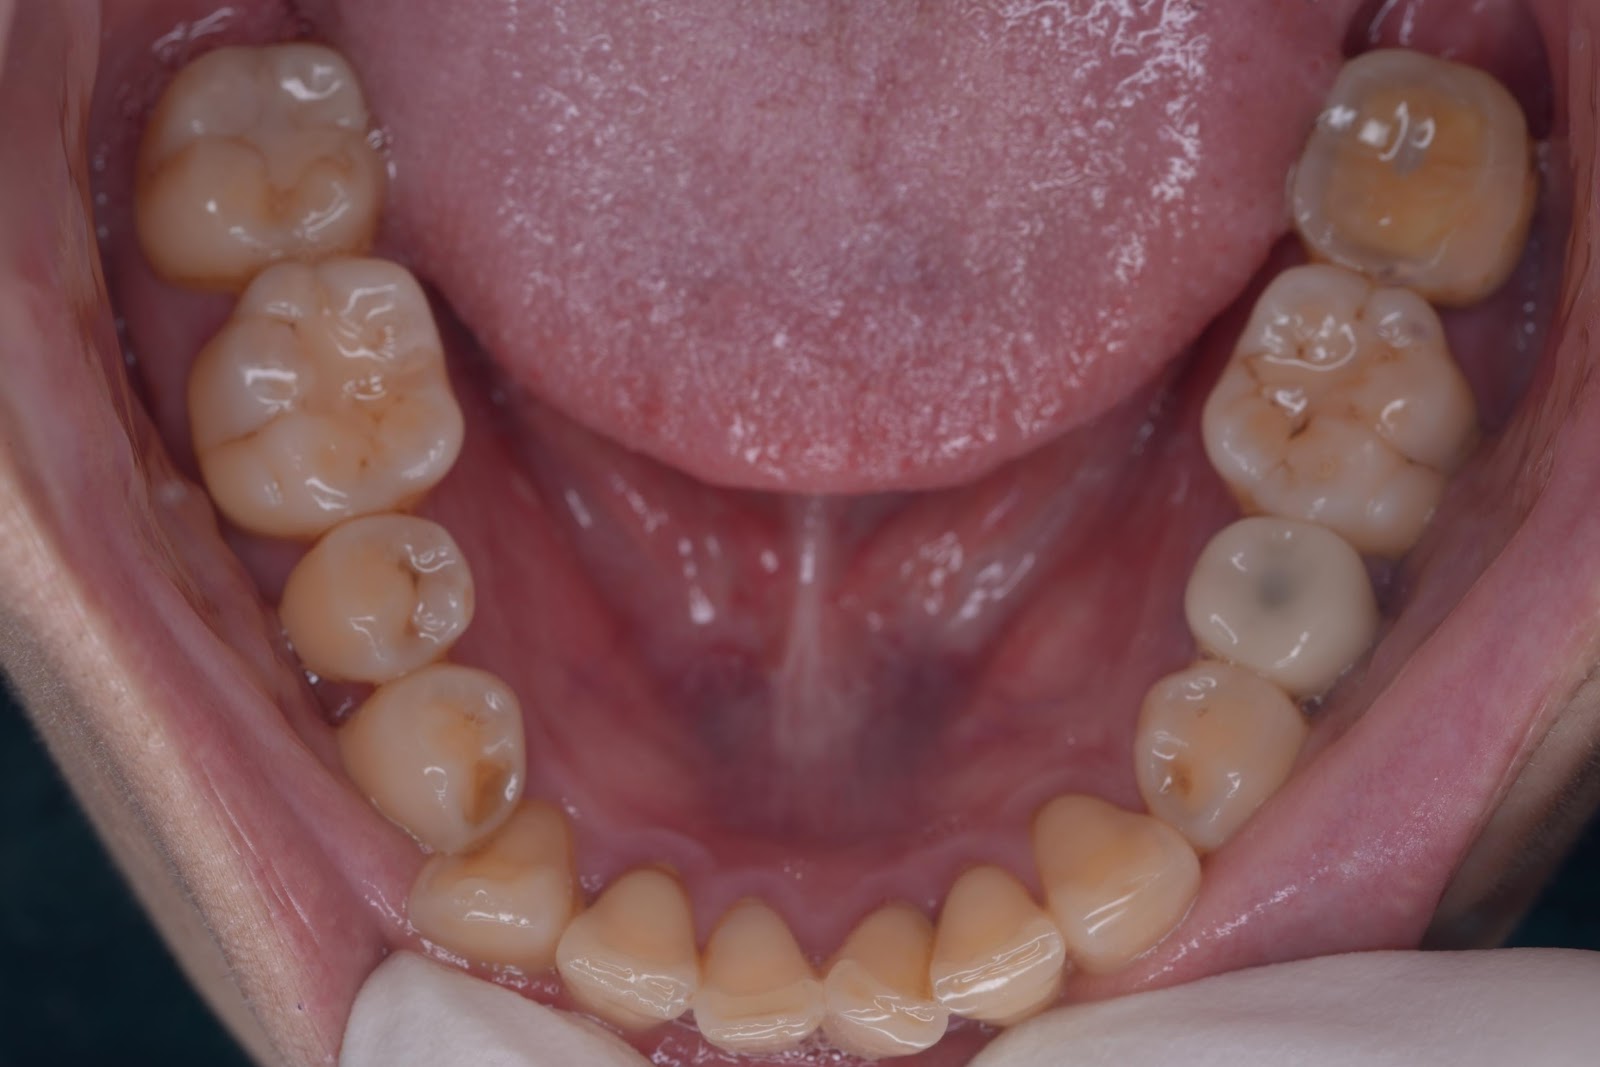

初診時